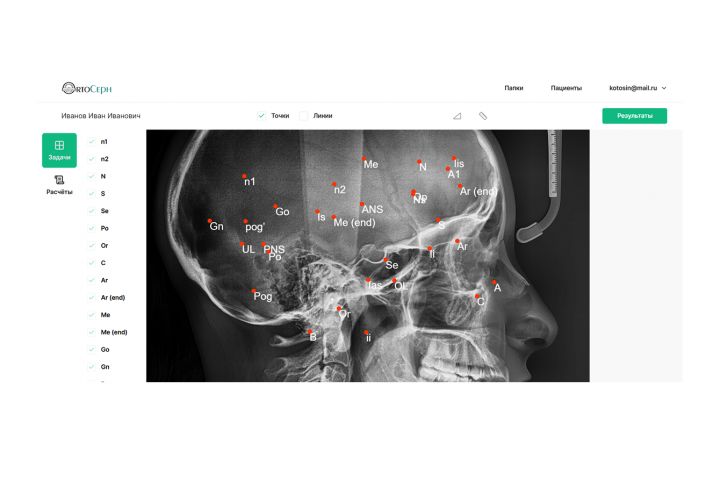

ПО на анализа рентген-снимков для врачей ортодонтов

Медилайт — современный диагностический центр, специализирующийся на 2D/3D исследованиях челюстно-лицевой области, обратился к нам с ключевым запросом:

создать ПО, которое автоматизирует сложный и рутинный процесс построения ТРГ-анализов (телерентгенография), — критически важный этап в работе ортодонтов при планировании лечения, в частности, при установке брекет-систем.

До внедрения решения врачи проводили ТРГ-анализ вручную, что:

занимало от 30 до 60 минут на одного пациента;

требовало высокой квалификации;

повышало риск ошибок и замедляло диагностику.

Сложность проекта заключалась во множестве систем расчета и подходов. Мы потеряли около 3 месяцев на разработку математического аппарата и не помогли понять, почему на выходе значения отличаются от необходимых. Причина нас в буквальном смысле шокировала, нашли ошибку в формуле в методическом материале, который нам предоставили заказчики. По итогу, теперь данное ПО показывает самые точные расчеты на рынке подобных программ и успешно эксплуатируется врачами центра.